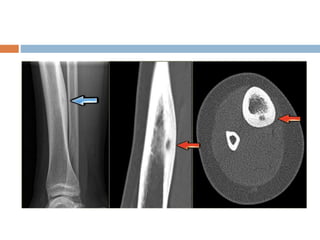

Xray

 Well demarcated radiolucent area in

metaphysis

 often extending upto physeal plate

 Cortex may be thinned and bone expanded.

 Well defined radiolucent cyst

 Trabeculated and eccentrically placed

 In growing tubular bone, vertebrae and flat

bones

 In adult may confuse with GCT

 Marked ballooning of bone end